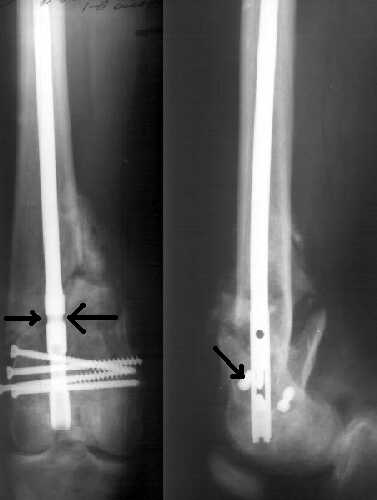

Если бы - есть заметная подвижность. Даже по снимку видно - отломки сдвинулись прилично, судя по положению частей стержня. Ну и при осмотре - качается...

If we should look for "hairs in an egg", we can see that distal fragment is a little flexed and (perhaps) valgus.

First deviation could be corrected by removing at first the screw with black arrow.

Another little imperfection is the small size of the nail and large holes (see the other black arrows) just on the fracture line : these mechanically make the nail less resistant and, if weigh bearing is full, they could be a cause of failure.

If your patient will be prudent, fracture will heal very well.